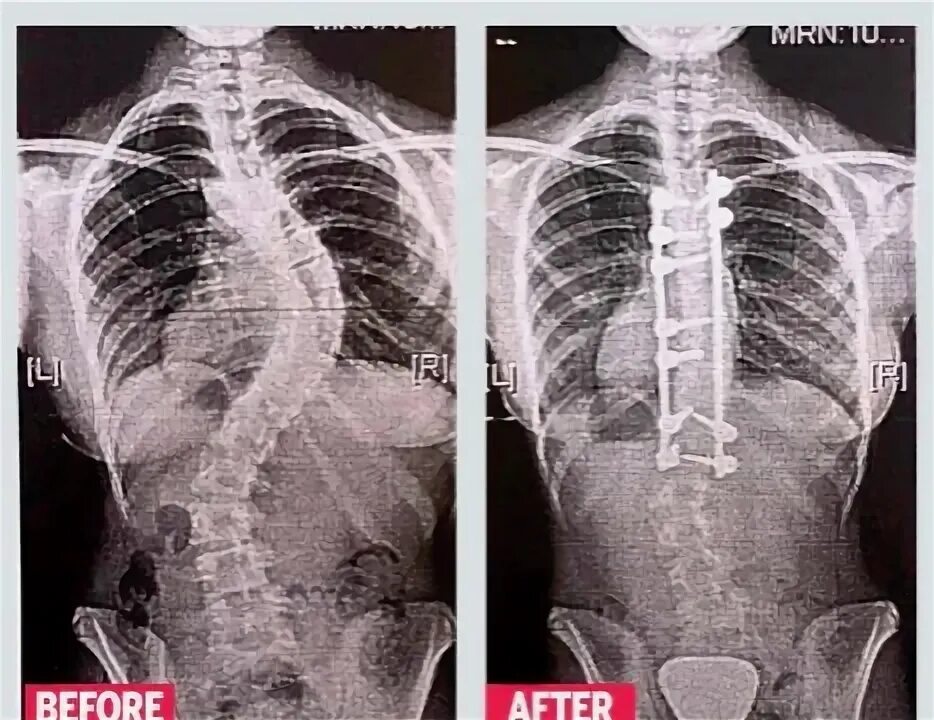

Операция по исправлению сколиоза